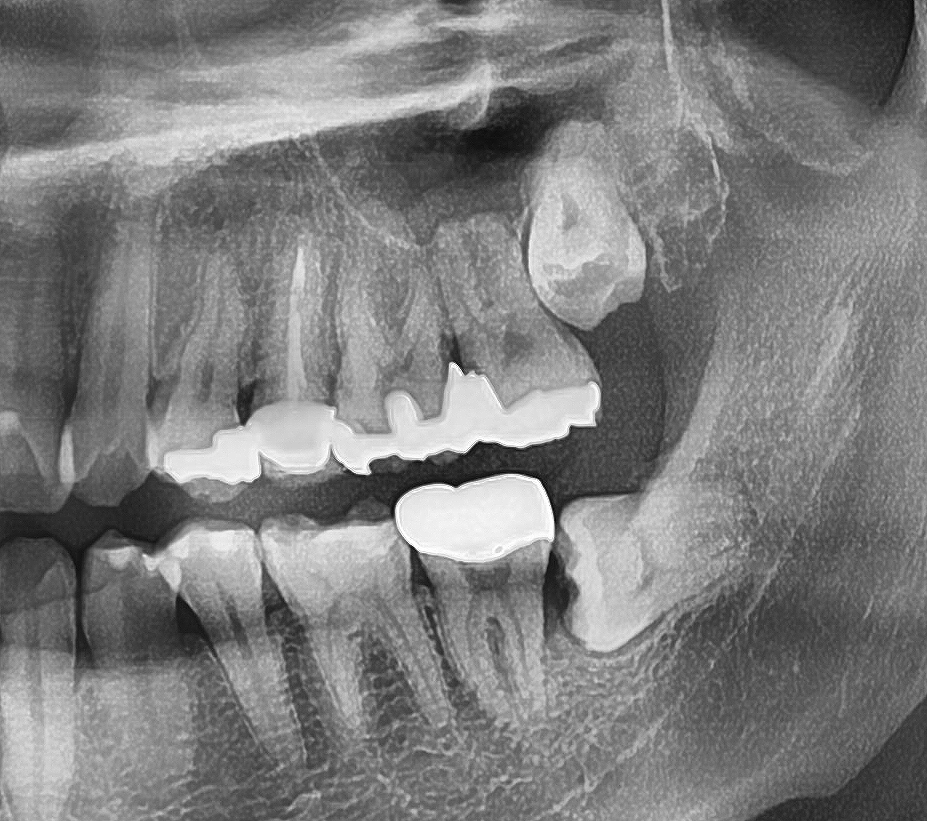

파노라마와 치근단 엑스레이를 찍어봤더니

위아래 양옆 4개를 가지고 있었고,

그 중 왼쪽을 아파해서 그 걸 먼저 뽑기로 결정했죠.

엑스레이를 찍어보니 완전 수평으로 누워있었어요.

딱 봐도 어려워보이는 케이스였죠.